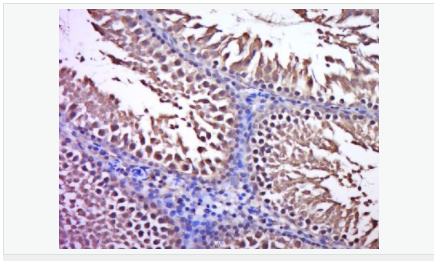

產(chǎn)品應(yīng)用WB=1:500-2000 ELISA=1:5000-10000 IHC-P=1:100-500 IHC-F=1:100-500 ICC=1:100-500 IF=1:100-500 (石蠟切片需做抗原修復(fù))

細(xì)胞定位細(xì)胞漿

產(chǎn)品介紹C3orf32 (chromosome 3 open reading frame 32), also known as fls485, is a 353 amino acid protein encoded by a gene that maps to human chromosome 3p26.1. Chromosome 3 is made up of approximately 214 million bases encoding over 1,100 genes. Notably, there is a chemokine receptor gene cluster and a variety of human cancer related loci on chromosome 3. Particular regions of the chromosome 3 short arm are deleted in many types of cancer cells. Key tumor suppressing genes on chromosome 3 encode apoptosis mediator RASSF1, cell migration regulator HYAL1 and angiogenesis suppressor SEMA3B. Marfan Syndrome, porphyria, von Hippel-Lindau syndrome, osteogenesis imperfecta and Charcot-Marie-Tooth disease are a few of the numerous genetic diseases associated with chromosome 3.

Expressed in enterocytes of small and large intestinal mucosa (at protein level). Expressed in enterocytes, chromaffine and interstitial cells.